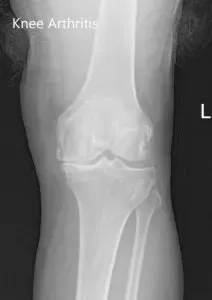

The range of motion of the left knee was full, with painful end flexion. Coronal, sagittal and rotational stress tests for instability were negative. There was no distal neurological deficit. Bilateral lower extremity pulses were 2+ and comparable. Examination of the right knee, bilateral hip, and bilateral ankles were normal. Imaging studies revealed the presence of bilateral tricompartmental osteoarthritis.

Preoperative X-ray images showing AP and lateral images of the left knee revealing tricompartmental osteoarthritis and severe medial joint space reduction.